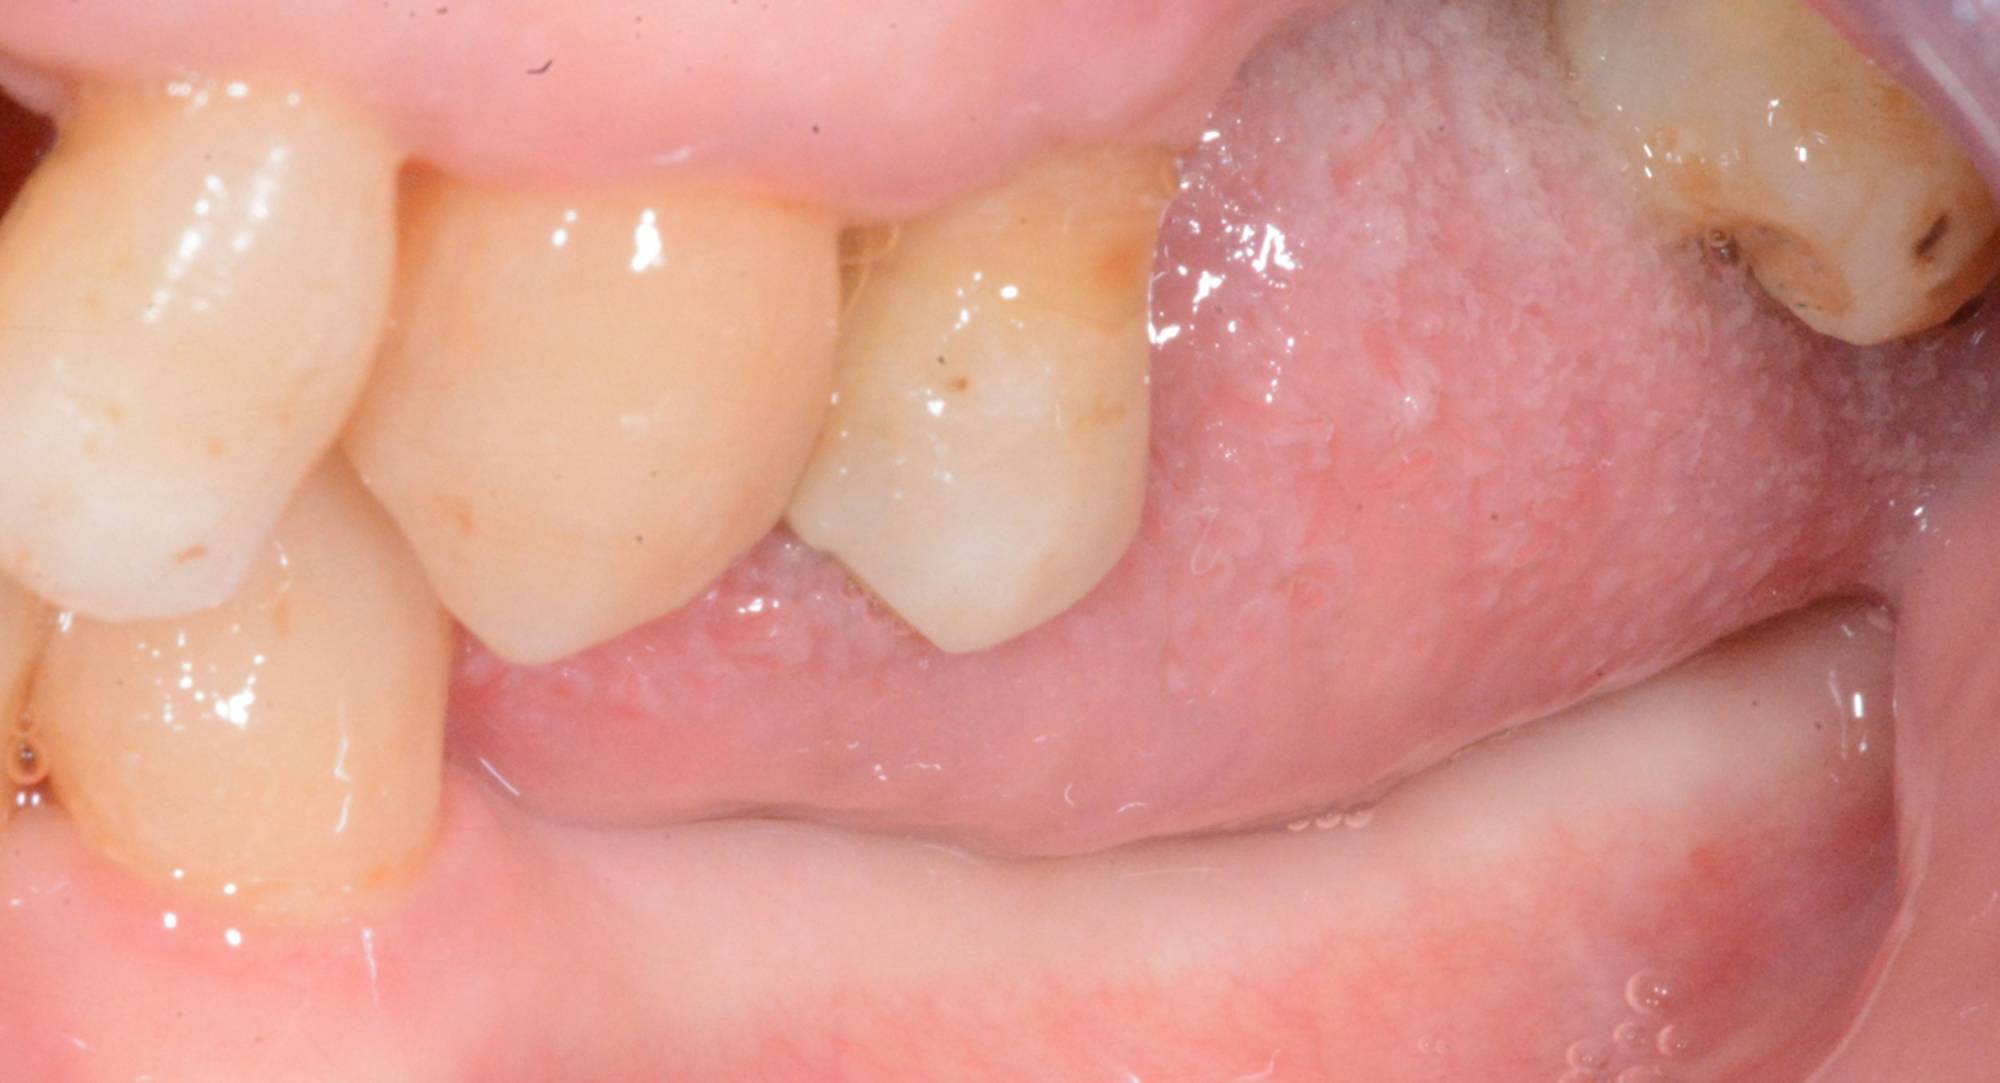

Tuttavia, in alcuni casi selezionati, è possibile protesizzare gli impianti subito dopo il loro posizionamento, nel giro di pochi giorni o addirittura nel corso della stessa seduta: questa tecnica è definita “carico immediato” e consente al paziente di entrare in Studio con la sua vecchia dentiera e di uscire il giorno stesso con una protesi fissa.